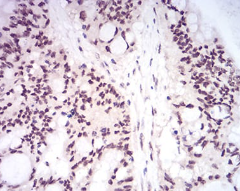

IHC    1/200 - 1/1000